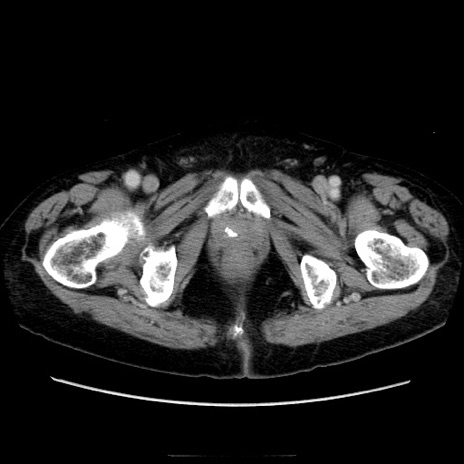

症例21(横断像)

【症例】70歳代男性

【主訴】腹痛

【現病歴】肝硬変・肝細胞癌にてかかりつけの方。約9時間前に食後より腹痛出現。症状が徐々に増悪し、嘔吐出現したため来院。

【既往歴】肝硬変、肝細胞癌(RFA、TACE後)

【身体所見】意識清明、表情苦悶様、BT 36℃、BP 129/78mmHg、P 88bpm、SpO2 97%(RA)、右上腹部から心窩部にかけて圧痛あり、反跳痛なし、筋性防御あり。

【データ】WBC 5800、CRP 0.16